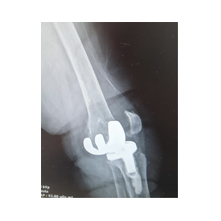

Aşınmış, hasar görmüş ya da eklem yüzeyleri tamamen bozulmuş diz ekleminin, yapay bir eklemle değiştirme işlemidir. Ameliyatta, ağrıya neden olan hasarlı kemik ve kıkırdak dokular çıkarılarak; yerine metal ve özel plastikten yapılmış, uzun ömürlü bir protez yerleştirilir. Bu sayede diz, tekrar ağrısız ve stabil bir şekilde çalışır hale gelir.

Eklem yüzeyleri özel kılavuzlar yardımı ile temizlendikten sonra metal protez eklem yüzeylerine bir kemik çimentosu ile adapte diyoruz. Bu iki metal yüzeyin sürtünmesini azaltmak için polietilenden yapılmış özel bir plastik tabakayı sisteme dahil ediyoruz.